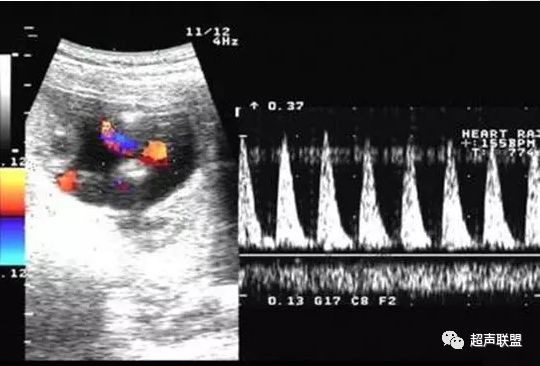

图1 正常脐动脉血流频谱